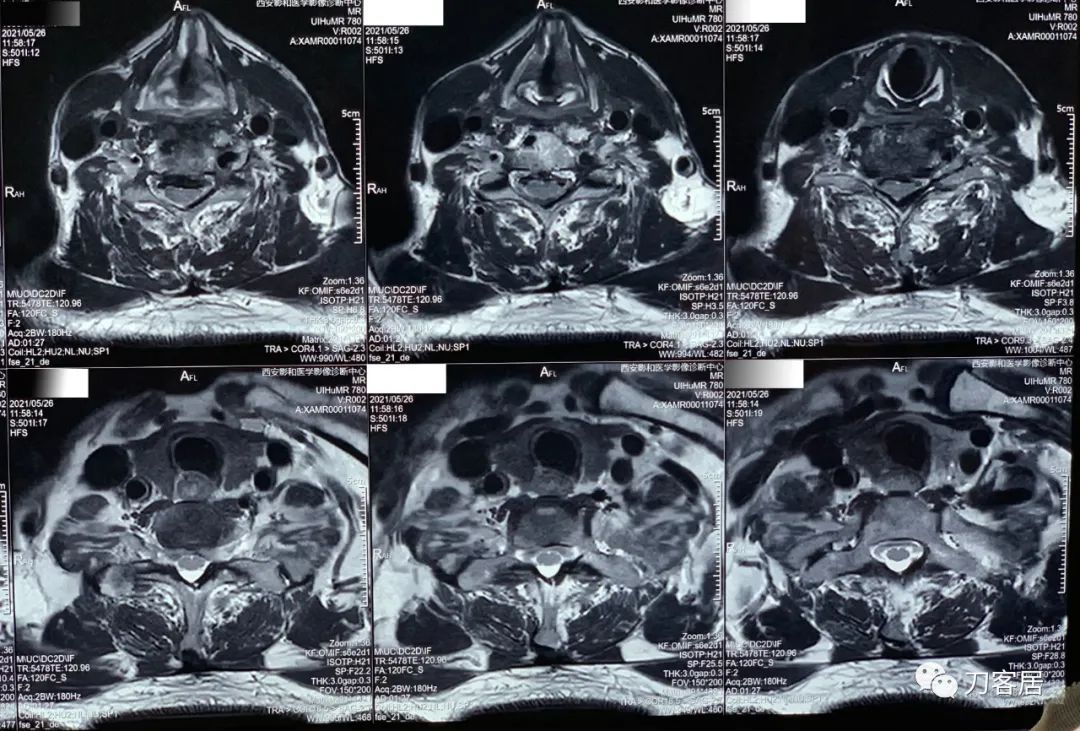

20210526-颈椎MRI经椎间盘横截面扫描。